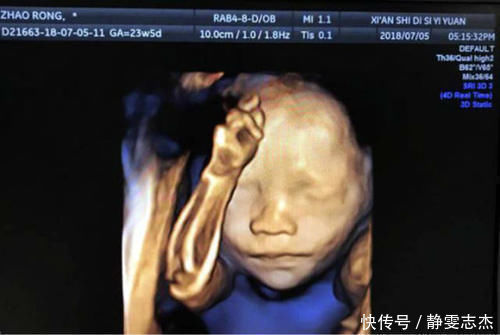

原来,怀孕6个月的时候,王潇和老公一起到医院产检并且做了四维彩超,因为早就知道四维彩超可以呈现出孩子的样貌,所以夫妻俩心里又紧张又期待,特别好奇孩子的样子。

但出乎意料的是,宝宝的“四维照”并不符合他们的期待,尤其是在老公眼里,他感觉这孩子谁也不像,全身都是皱巴巴的,尤其是鼻梁塌陷,看起来太丑了。

四维彩超是产科检查的一个项目,它可以观察到胎儿的表情、长相,还可以直观地呈现胎儿在母体中的肢体运动。

不过,四维彩超成像的清晰度不是固定的,它和怀孕周期、宝宝是否配合、胎位如何以及妈妈的腹部脂肪等都有着关系,而且宝宝在羊水中时皮肤是呈褶皱状态的,正如王潇的孩子那样,所以父母看到小宝宝这样时不必大惊小怪。